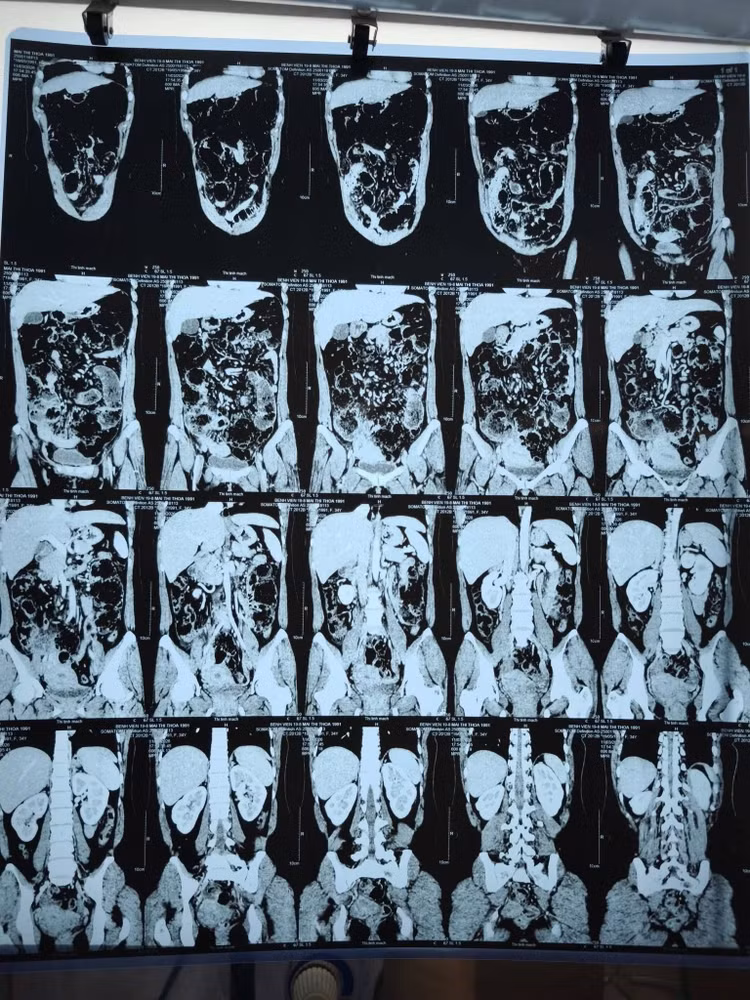

Hình ảnh đa túi thừa trên phim chụp - Ảnh BVCC

Kết quả chẩn đoán ban đầu qua CT Scanner gây nhầm lẫn với tắc ruột do bã thức ăn. Đây là một "cái bẫy" hình ảnh học phổ biến vì túi thừa chứa phân non rất dễ bị nhầm với khối bã thức ăn.

Chẩn đoán hình ảnh CT Scanner là công cụ quan trọng nhất để phát hiện đa túi thừa - Ảnh BVCC

Chẩn đoán hình ảnh CT Scanner là công cụ quan trọng nhất, nhưng cần sự phân tích tỉ mỉ từ bác sĩ để phân biệt túi thừa với các nguyên nhân tắc ruột khác.